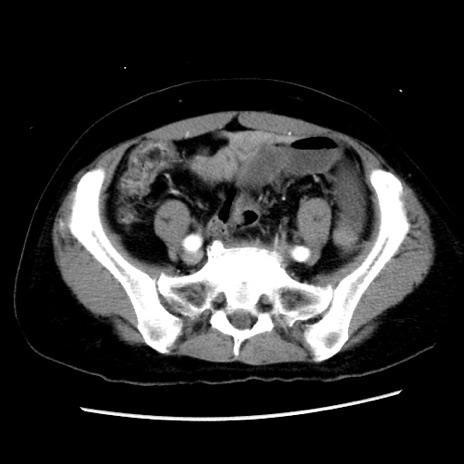

症例10(横断像)

【症例】 50歳代女性

【主訴】 腹痛

【現病歴】前日生レバーを食べた。今朝に排便あり。 昼前に突然発症の腹痛を生じ、当院救急外来を受診した。

【既往歴】 子宮筋腫にてで子宮全摘後

【身体所見】 意識清明、腹部:平坦、軟、下腹部やや左を中心に圧痛・反跳痛あり、筋性防御あり

【データ】WBC 7800、CRP 0.07